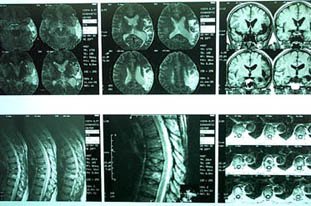

Уважаемые участники форума, Больной 53 лет, с жалобами на выраженные боли в области грудного отдела позвоночника, чувство онемения и стягивания в правой кисти, боли в мышцах конечностей и туловища. Отмечается парез правой верхней конечности.

В декабре 99 года перенес геморрагический а потом и ишемический инсульт левой задне-лобно-височной области. Выписался со значителсным улучшением неврологической симптоматики. Через год, на фоне обычного самочувствия, пожаловался на боль в спине, после чего появилось тоническое напряжение правой руки, половины туловища, перерастающее в приступ с судорогами по типутонико-клонических и потерей сознания. Госпитализирован. На CТ выявлен большой очаг в виде кистозной полости. Компрессионный перелом 8-9 грудных позвонков. В последующем, на протяжении полутора лет в общей сложности отмечено 5 аналогичных по формуле припадков. Падения с высоты во время приступов небыло. Также отрицает травмы позвоночника в анамнезе. ПовторнаяR-графия и СТ позвоночника выявила патологический компрессионный перелом и остеопороз тел Th 6; 7; 8; 9, (отрицательная динамика). Наличиенеобластомного процесса не выявлено. Все анализы, включая паратгормон, впределах нормы кроме:Са-Т - 2.66 (от 2.02 до 2.60)Р - 1.72 (от 081 до 1.62)СОЭ - 34мм/часСнимки 1, 2, 3, 4 прилагаются.Возникает ряд вопросиов: Может ли деструкция в левой задне-лобно-височной области быть связана с системним остеопорозм позвонков и пат. переломом? Моигут ли эпилптические приступы явиться причиной компрессионного переломапозвонков? Какие дополнительные исследования нужны для дифдиагностики болезни Куммелля? Тактика лечения (корсет?), показания и противопоказания к хирургическому вмешательству на позвонках в данной ситуации Прогноз?Буду благодарен любым соображениям,Аршак Мирзоян